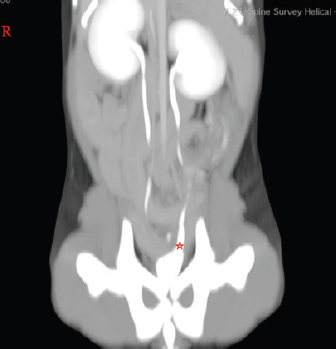

The CT scan was performed on a GE BrightSpeed 8 CT machine. The patient was positioned with the head pointing to the gantry in dorsal recumbency. Anesthesia was maintained with isoflurane gas flowing through a fourth-size endotracheal tube. A helical scan acquisition was performed through points of I (eight thoracic vertebra) through S (the caudal portion of os pubis) with slice gaps of 1.25 mm. A total of 448 images were taken twice—pre and post-contrast medium infusion (iohexol, Omnipaque ® 647 mg/ml–2.4 ml i.v.). Analyzing soft tissue reconstructions in transverse, sagittal, and dorsal planes of the CT tomograms, we found that the left ureter opening is pathological (Fig. 1).

Fig. 1. Post-contrast dorsal reconstructed CT study image. Red star indicates the caudal portion of the left ureter, which is expanded and might indicate a forming mild hydroureter.